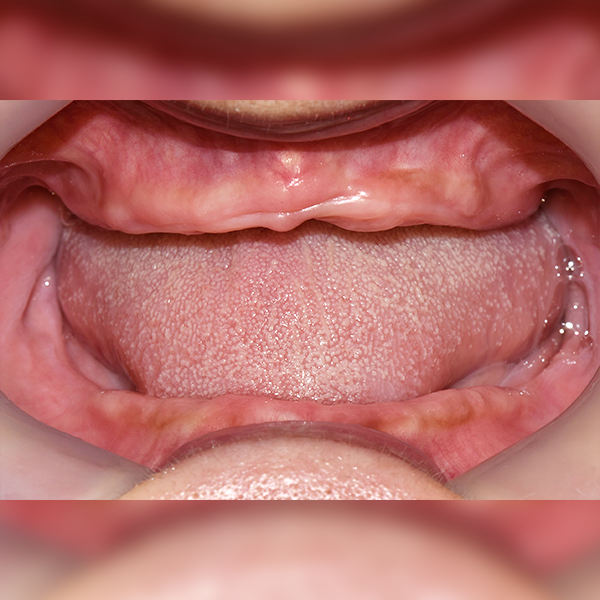

전악/전체 / 뼈이식|수면

Case.15 60대 김*은 2018-08-02 / 2019-05-30

After After

Before Before